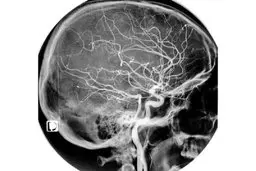

علائم سکته مغزی

هشدار به جوانان | علائم سکته مغزی

سکته های مغزی ایسکمیک که اکثریت سکته های مغزی را تشکیل می…

درمان سکته مغزی و زوال عقل با "اطلس سلولی"

به نظر میرسد که بسیاری از انواع زوال عقل از جمله آلزایمر،…